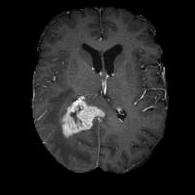

(a) (b) (c) (d)

Boundary Stream:

Fig. 2 demonstrates the output of each of the attention layers in our dedicated boundary stream. In essence, each attention layer progressively localizes the tumor and refines the boundaries. The first attention layer has learned rough estimate of the boundaries around the tumor and localized it, whereas the second and third layers have learned more fine-grained details of the edges and boundaries, refining the localization. Moreover, since our architecture leverages a dilated spatial pyramid pooling to merge the learned feature maps of the regular segmentation stream and the boundary stream, multiscale regional and boundary information have been preserved and fused properly, which has enabled our network to capture the small structural details of the tumor.

(a) (b) (c) (d) (e)

Comparison to Competing Methods:

We have compared the performance of our model against the most popular deep learning-based semantic segmentation networks, U-Net [9] and V-Net [7] (Fig. 3). Our model outperforms both by a considerable margin in all evaluation metrics. In particular, U-Net performs poorly in most cases due to the high false positive of its segmentation predictions, as well as the imprecision of its boundaries. The powerful residual block in the V-Net architecture seems to alleviate these issues to some extent, but V-Net also fails to produce high-quality boundary predictions. The emphasis of learning useful edge-related information during the training of our network appears to effectively regularize the network such that boundary accuracy is improved.